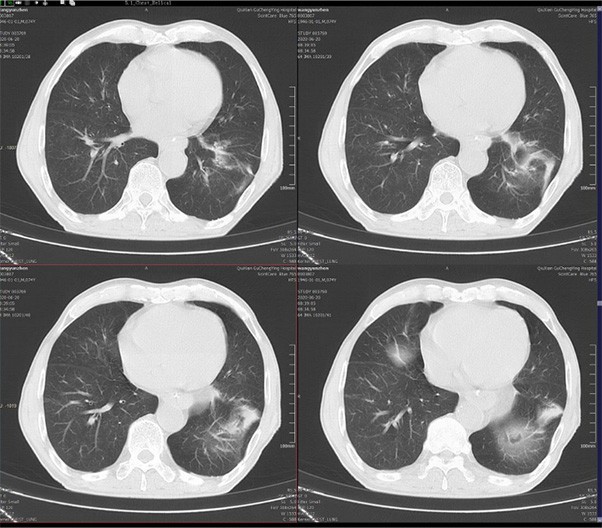

ScintCare Blue 755 incorporates an entirely digital integrated ScintiStar detector, which was solely developed by MinFound, from material to the whole structure design, based on the technical know-how of our skilled scientific team. The system produces high-resolution images with a low radiation dose and an excellent signal-to-noise ratio.

NDI NanoDose iteration algorithm is an innovative iterative technique for image reconstruction that takes full advantage of deep learning in anatomical structure in image space as well as model-driven iteration involving tube and detector in projection space, with the aim to generate sharp images in high resolution at the lowest possible dose.

臨床畫廊